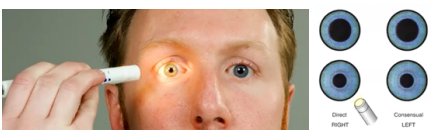

P-E-R-R-L-A (Pupils Equally Round, Reactive to Light Accommodation)

testing pupillary reaction to light (direct and consensual)

testing pupillary reaction to light (direct and consensual)

Pupillary reaction to light

Twelfth Step of Eye Assessment

Darken the room and ask client to focus on a distant object

Shine a light obliquely into one eye and observe the pupillary reaction

How to test 12. Pupillary reaction to light?

Left Eye (Oculus Sinister)

3 - Pupil’s eye at rest

2 - Constricted size

How to interpret result of O.S. 3/2 in 12. Pupillary reaction to light?

Constriction of the pupils

Normal Finding for 12. Pupillary reaction to light

Monocular Blindness

Both pupils constrict

Abnormal Findings for 12. Pupillary reaction to light

Monocular Blindness

Abnormal Findings for 12. Pupillary reaction to light

Light directed to the blind eye results in no response in either pupil